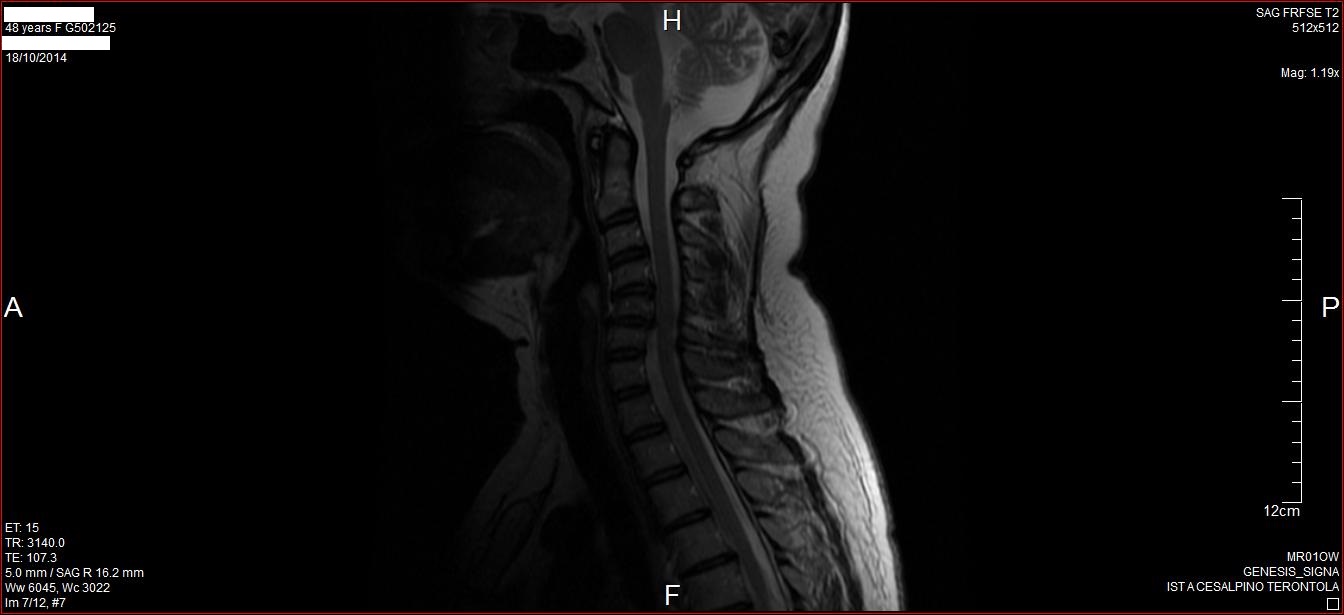

La RM dell'encefalo/rachide cervicale evidenzia:

1) inversione cifotica nel tratto intermedio

2)piccola area di alterato segnale puntiforme di significato microangiopatico nella sede encefalica

3) discopatia degenerativa in C5-C6 con protrusione discale posteriore ad ampio raggio complicata de piccola ernia ad estrinsecazione posterolaterale e preforaminale sinistra che determina un restringimento dell'imbocco della corrispondente forame di coniugazione con contatto della parte distale della tasca radicolare C6 di sinistra

4) discopatia degenerativa C4-C5 con modesta protrusione discale posteriore ad ampio raggio che contatta appena il sacco durale senza efetti comprensivi sul midollo con minimo impegno nella parte bassa di entrambi i forami di coniugazione.

Iniziali alterazioni degenerativi di natura artrosica nel tratto cervicale distale. Nessuna altra alterazione a livello cervicale, alle formazioni anatomiche della cerniera cranio vertebrale ed encefalo-midollare ed ai primi metameri di rachide e midollo dorsali. Congenitamente normali i diametri sagittali del canale e del sacco durale. Regolare la morfologia del midollo e degli spazi subaracnoidei perimidollari.

Sono molto preoccupata per questi muovimenti che non posso controllare assolutamente e mi vengono anche da seduta in chiesa. Andrò da un neurologo più presto possibile però mi farebbe piacere avere un parere. L ernia cervicale può produrre questi scatti oppure devo cercare la causa in altra parte? Allego una immagine dalla RM. Ringrazio anticipatamente, Viola

Gentile Sig.ra Viola, ho visto l'immagine di RMN cervicale che evidenzia una inversione della fisiologica lordosi.Andrebbe visto tutto l'esame per poter dire se ci sono ernie significative ma che comunque a mio avviso non possono dare un quadro sintomatologico così come lei lo descrive. credo sicuramente che il neurologo possa rispondere alle sue domande con maggiore competenza.